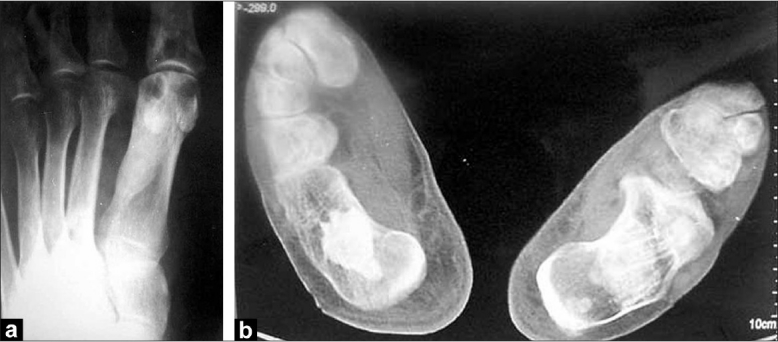

A 42-year-old male patient presented in 2001 with urinary symptoms. His physical examination was unremarkable, with normal pulse and blood pressure. Investigation at presentation revealed a normal hemogram and erythrocyte sedimentation rate (ESR). Fasting blood sugar was 90 mg/dL (normal, 90-110 mg/dL), and kidney functions were normal. Ultrasonography revealed grade one benign prostatic hyperplasia with multiple cysts in left kidney. Isotopic Renogram done after intravenous injection of 5 milli Curies of Technetium-99m diethylene triamine penta acetic acid (Tc-99m DTPA) under a large field of view Gamma camera revealed a relative renal function of 45% in left kidney and 55% in the right kidney [Figure 1]. The overall scan impression was that of an enlarged left kidney with mild functional impairment. On reevaluation in 2003, his physical examination was unremarkable. Investigations revealed a normal hemogram, normal results of kidney function tests and normal levels of serum and urinary calcium. Parathormone (PTH) levels were within normal limits. Intravenous pyelogram (IVP) revealed a well-defined cystic lesion in the left kidney near pelvicalyceal system causing splashing of pelvis, obstructed calyces and caliectasis. Contrast-enhanced CAT scan of abdomen (CECT) revealed large multiloculated cystic mass arising from left kidney, impinging on pelvis and causing hydronephrosis [Figure 2]. Fine-needle aspiration was inconclusive. Tc-99m Methylene Diphosphonate (MDP) bone scan revealed abnormal tracer uptake in multiple ribs, femur, pelvis, foot bones, tibia and 9th, 10th and 11th dorsal vertebrae [Figure 3]. Hemogram and serum chemistry were normal. Left radical nephrectomy was done in April 2003. Operative findings revealed a mass involving left kidney, with hydronephrotic changes. Histopathological examination (HPE) revealed arterial malformation of kidney [Figure 4]. Patient was referred to tertiary care center with an impression of renal cell carcinoma with diffuse bone metastasis. He was reevaluated and found to have high serum alkaline phosphatase (Alp) levels. In view of the long history, good performance status and histopathological examination, skeletal survey was done, which revealed hyperostosis of long bones, and the bone of foot resembling wax dripping on one side [Figure 5]. A final diagnosis of melorheostosis was made and the patient reassured. He is on our follow-up for the last 5 years and is asymptomatic.

| Figure 5 (a, b) Irregular, hyperosteotic changes of cortex, resembling melting wax dripping on the side of a candle. Dense sclerotic linear areas are seen, mainly in the cortex